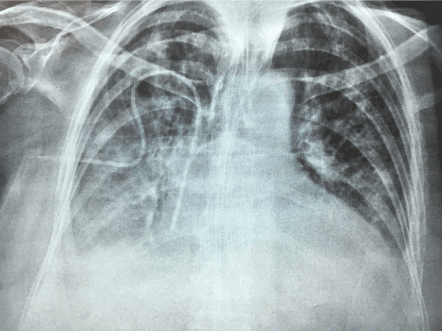

We present a unique case of a 82 years old women, with this newly described condition called “pseudomembranous enterocolitis cured with three transplants of intestinal microbi0ta (imt).” We evaluated the case of gaw, who had a perforates sigmoid diverticulum 10m days ago and had surgery with sigmoid resection, colostomy and hartmann’s pouch. Her progress was good. However, she was given metronidazole and vancomycin, antibiotics that caused severe diarrhea and toxic state, a week postoperatively. Histopathological study of surgical specimen showed colonic mucosa extensively ulcerated and granulation tissue, fibrin and abundant neutrophils. Submucosal edema and acute periserositis. The muscular and mucosal layer had not alterations. A diagnosis of pseudomembranous enterocolitis (pm) was made. The patient had a toxic state, semi-conscious, diaphoretic and extensive erythema in the right forearm, with minor erythema at the left forearm and face, as well as perineal erythema, third degree edema in lower limbs, dehydrated and chest x-ray showed interstitial pneumonitis.  She had a typical case of pm, and proceeded to perform an intestinal microbiota transplantation (imt) from healthy donors at clinical and laboratory studies. After that imt we performed colonoscopy, which showed at the course of transverse and right colon multiple plaques of whitish, cotton-like appearance, which protuded on the mucosal surface. This appearance were also seen at the left colon. We applied 400 ml. Of imt in the right colon and 100 ml at the hartmann’s pouch of rectum. At the colonoscopy we placed a foley’s catheter with an inflated balloon 20 ml. Also, solid petroleum jelly was left to prevent imt elimination. We removed all antibiotic treatment and replaced with probiotics, through the nasogastric tube.

Three days later, a new imt was required under the same conditions as the former two imt. On this occasion the patient was fully aware, speaking and responded correctly to our questions. She had no erythema in her body, no edema at her legs and her chest x-ray had no pneumonitis, and showed only a small leak at the base of right lung.

Figure 5. The chest X-ray shows right basal opacity, with atelectasis lines.

Figure 6. Radiographic control (post-transplant has improved substantially). Only discreet right basal effusion.